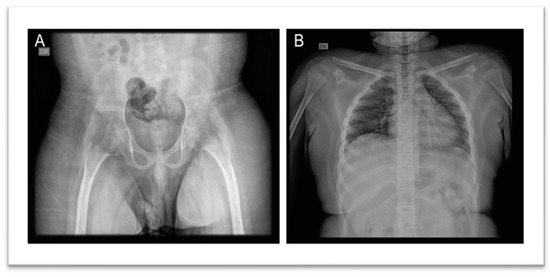

Imaging studies included a Brain Magnetic Resonance Imaging (MRI), which revealed calcification in the anterior aspect of the falx cerebri, hyperostosis of the inner calvaria table in the frontotemporoparietal regions, and asymmetry of the petrous apices, with the right side showing an area of T2 hyperintensity, without expansive effect, contrast enhancement, or diffusion restriction, potentially indicative of a mucocele or effusion (Figure 3). Radiographs of the pelvis, lower limbs, knees, and ankles showed bilateral cortical thickening of the diaphysis of long bones with areas of apparent bilateral and symmetrical hyperostosis (mid/distal femur diaphysis, proximal and distal tibia and fibula), with no significant difference in limb length (Figure 4).

Figure 3. Brain Magnetic Resonance Imaging: calcification in the anterior aspect of the falx cerebri, hyperostosis of the inner calvaria table in the frontotemporoparietal regions, and asymmetry of the petrous apices.

Figure 4. Radiographic Images of the pelvis, lower limbs, knees, and ankles: Bilateral cortical thickening of the diaphysis of the long bones with areas of apparent bilateral and symmetrical hyperostosis (mid/distal femur diaphysis, proximal and distal tibia and fibula).